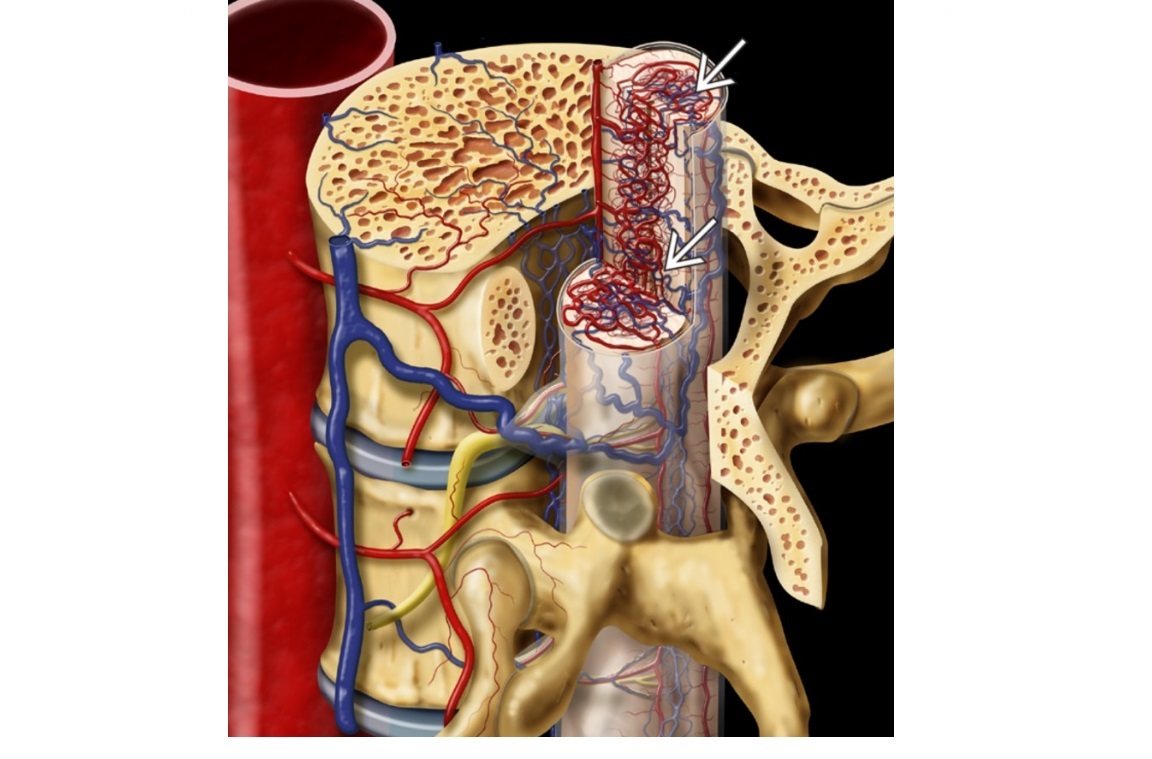

SAH and MRI shows intramedullary nidus. what type of spinal AVMs?

A

Type 2

INTRAMEDULLARY NIDUS. Present with SAH

From anterior or posterior spinal arteries

Associated with cutaneous angiomas - HHT and KTS